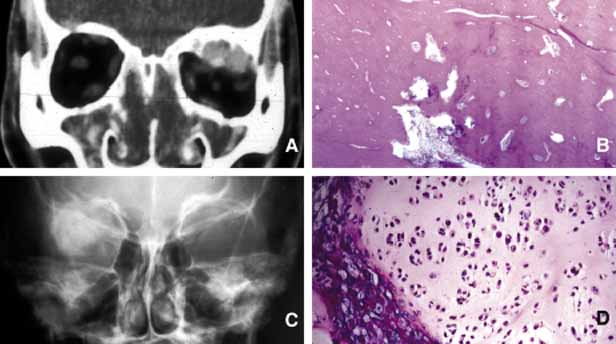

ANOPHTHALMOS/MICROPHTHALMOS When the globe is abnormally developed, microphthalmos, congenital cystic eye, and extremely rarely, anophthalmos occur. Microphthalmos usually occurs as a unilateral condition and in approximately 10% of cases it is associated with other craniofacial malformations including agenesis of the corpus callosum, polymicrogyria, and mid-line arachnoidal cysts. Microphthalmos may be seen as a part of several genetically determined neuronal migration disorders such as Walker-Warburg syndrome, Aicardi syndrome, and Fukuyama congential muscular dystrophy.9,10 In cases of microphthalmos and anophthalmos the orbit may be well formed but does not develop to a full adult volume. The mechanism by which the presence of the globe effects the growth of the orbit is not well understood. Microphthalmos may be associated with a colobomatous cyst as a result of the abnormal closure of the embryonic optic fissure leading to the prolapse of neuroectodermal tissues into the orbit (Fig. 1) This cystic structure may increase rapidly in size to overshadow the abnormal globe and may be confused with a neoplasm. When cystic lesions in the orbit are suspected imaging studies should be performed not only to look for other intracranial abnormalities but also to establish the possible connection of the cyst to the colobomatous globe versus to abnormally formed meninges.11 Macrophthalmos (buphthalmos) may also rarely develop as a congenital anomaly in patients with Sturge-Weber syndrome and rarely in neurofibromatosis type I. ORBITO-CRANIAL MALDEVELOPMENTS Cephalocele results from the extension of maldeveloped CNS tissues including meninges (meningocele), brain parenchyma (encephalocele), and the combination of the two (meningoencephalocele) into the orbital cavity.12,13 Intraorbital cephaloceles may develop anteriorly at the suture lines of orbital bones or posteriorly extending into the orbit from orbital fissures and the optic canal. Depending on the combination of these herniations they contain brain and/or meningeal tissues (Fig. 1). Aberrant fibroglial tissue has also been described in the orbit.14 Hamartoma is a tumor-like proliferation of tissues that normally exist at a given body location. The best examples of orbital hamartomas are the vascular hamartomatous lesions that are composed of vascular elements including capillary endothelial cells, distended or collapsed cavernous blood and lymph vessels, tortuous arterial and venous channels with or without anastomoses, etc. Other examples of hamartomatous orbital tumors include neurofibroma and lipomatous hamartoma.15 Choristoma, however, is a tumor-like proliferation of tissues that are not normally present at a given body location. The most commonly encountered example of orbital choristoma is a dermoid.16 Dermoids that present with many varieties result from the entrapment of epithelial structures at the site of closure of fetal fissures. Superficial dermoid cysts occur primarily subcutaneously anterior to orbital septum or within the anterior orbit. If the cyst wall is made of epidermis without dermal tissues, it is classified as an epidermoid cyst. These lesions are occasionally lined by conjunctival or pseudostratified respiratory epithelium.17 The superficial lesions must be distinguished from deep orbital dermoids that are usually rounded, encapsulated tumors filled with fatty materials, keratin, and dermal structures such as hair particles. Histopathologically the dermoid wall is lined by keratizing squamous epithelium with dermal appendices including hair follicles and sebaceous and eccrine glands.18 Most of the dermoids are well outlined by ultrasonography because of their anterior location thus making CT or MRI rarely necessary.19 If the dermoid is unusually large or located at the frontal zygomatic suture, CT is necessary to document the relationship of the lesion to the bone before surgical intervention. Rarely, dermoids at the fronto-zygomatic suture may develop dumbbell-shaped lesions partially within the orbit and partially extending into the temporal fossa.20,21 Unusually large superior orbital dermoids particularly those that leak and create granulomatous reaction within adjacent soft tissues may erode the bone and extend into the frontal sinus or the cranium (Fig. 2). ORBITAL TERATOMA Teratoma is a germ-cell tumor that contains tissues derived from endoderm, ectoderm, and mesoderm22 (Fig. 1). Therefore, these lesions may contain skin, bowel, lung, brain, thyroid, cartilage, and bone tissues. Most teratomas develop unilaterally and in girls. A majority of these congenital tumors are benign. Occasional reports have documented malignant transformation within orbitocranial teratomas.23 However, these benign tumors continue to grow after birth because of the collection of secretions from different tissues into the partially cystic spaces of the tumor. Some teratomas create massive proptosis and most can only be treated by exenteration. However, some of these lesions have recently been reported to be removed surgically with preservation of the globe and other vital orbital structures. TRAUMA Mechanical Injury Orbital injuries result from the absorption of kinetic energy that occurs whenever the orbital tissues contact an object moving at a different speed.25 The orbital rim is capable of absorbing a considerable amount of kinetic energy without being fractured. Yet, a variety of impact forces striking the orbit may result in fractures in different areas.26 The absorption of the kinetic energy by an orbital bone may lead to contusion and/or laceration of the skin and superficial soft tissues, local deformation of the adjacent structures, globe, orbital soft tissues and bones and increases pressure in the orbital cavity. A common end result of an orbital impact is the fracture of the floor and/or the medial wall (lamina papyracea)27 (Fig. 3). Fractures of other orbital bones occur less often. Foreign bodies may be introduced into the orbit at the time of injury and may cause secondary problems depending on the nature and the location of the foreign body.28 Some foreign bodies such as copper may cause tissue necrosis and degeneration (chalcosis), and others particularly organic matter, may carry organisms such as bacteria and fungi into the orbital tissues and cause secondary infections29 (Fig. 3). Once the fracture of an orbital bone occurs, it may produce sharp edges to lacerate adjacent soft tissue structures including the globe, optic nerve, other nerves, muscles, and vessels.30 Depending on the damage of the particular tissue, functional deficit results. Another issue to deal with in an injured orbit is the development of hematoma, hematic cyst, and cholesteotoma. Hemorrhage in the orbit may occur spontaneously without any physical exertion in healthy individuals. Although terminology is not very strict, hematoma usually refers to a localized collection of blood within orbital soft tissues that develops secondary to trauma. When the blood collection within the orbit becomes organized and surrounded by a thin pseudocapsule, it is known as a hematic cyst31 (Fig. 4). If the hemorrhage develops within an existing lymphatic or vascular tumor, these lesions are known as blood cysts or “chocolate” cysts.32 Hematic cyst consists of a localized collection of blood surrounded by a nonepithelium-lined thin fibrous capsule.33 These lesions usually develop within 1 to 2 weeks of orbital trauma but chronic cases may occur up to 20 years after orbital injury.34,35 They may reach to a size causing proptosis, extraocular motility disturbance, compression on the globe and optic nerve, that can easily be detected with ultrasonography, CT, or MRI. Hematic cysts may develop within the muscle cone or in the extraconal orbital locations.33–36 These cysts are lined by fibrovascular tissue at the periphery and contain degenerated erythrocytes, protein debris, and cholesterol crystals. In many instances the thin nonepithelial lining is adherent to the adjacent structures with fibrous tissue. Cholesteatoma is another cystic lesion that is confined within a “pseudowall” without an epithelial lining.37 Cholesteotomas are usually located in the superior lateral orbit within the lacrimal gland fossa. Imaging studies may show a cystic, semi-cystic, or a solid lesion within the diploe of the bone or within the orbital soft tissues, with or without erosion of the adjacent bone.38 Histopathologically the lesion is composed of cholesterol clefts, hemosiderin, and hematoidin granules, other blood breakdown products and fibrin surrounded by a mixed lymphohistiocytic infiltrate and multinucleated foreign body giant cells.39 On imaging studies these lesions appear as unilocular rounded masses with destruction of the adjacent frontal and zygomatic bones. Although bone involvement in general implies malignancy, the sclerosing character of the bony destruction in choleosteoma, which is best seen in bone window images, favors a benign lesion. Although bone destruction also makes one think along the lines of metastatic tumors, one should also consider benign lesions such as brown tumor, aneurysmal bone cyst, and ruptured dermoid. Multiple cuts of the frontal bone should be examined to rule out the possibility of intracranial extension. Osteomyelitis of the orbital bones evolving as a complication of paranasal sinusitis is another entity that should be considered in the differential diagnosis of cholesteotoma. In osteomyelitis the bone infection extends into the periosteal space and beyond. Precise delineation of the lesion can be performed with CT and MRI particularly in combination with bone SPECT, a sensitive technique used to detect osteomyelitis within cranial and orbital bones.40 Mucocele Although a commonly encountered space occupying lesion in the orbit, mucocele is technically not a neoplasm. It is a cystic cavity lined by pseudostratified respiratory epithelium prolapsing into the orbit from a paranasal sinus, most commonly the frontal followed by the ethmoidal sinus (Fig. 5). Primary mucoceles develop as a result of an inflammatory obstruction of the ostium of the paranasal sinuses. Secondary mucoceles, however, are most commonly seen after orbital trauma and surgery; they may also develop secondary to neoplasms of paranasal sinuses and nasopharynx. If there is a superimposed infection, the lesion is referred to as pyocele. The mucocele develops as a well delineated cystic structure originating from a paranasal sinus. Depending on the location, it may compress orbital structures including extraocular muscles, optic nerve, and the globe.41 Clinical presentation of the mucocele is usually with globe displacement and/or proptosis, extraocular motility deficiency, particularly in the direction of the sinus extension into the orbit, and other compressive symptoms.42 The crepitant or calcified hard wall of the mucocele may be palpated underneath the superior or medial orbital rim. Mucoceles in general, are rare in children, however, a unique variant, ethmoidal mucopyocele, is known to occur in the medial canthal area, with lateral displacement of the globe. On CT, mucoceles present as hypointense, expanding masses originating from the paranasal sinuses. Early in their development these lesions are small, mucous-containing cysts. Later they are characterized by crescent-shaped and thinned remodeling of the bony walls of the orbit and sinuses.43 On MRI, mucocele presents with different appearances depending on the amount of free water within its luminal contents. When the intraluminal mucous becomes inspissated, the signal intensity in both T1 and T2 images decrease, getting closer to normal air content of the sinus.44 Treatment of mucocele is surgical excision. Other injuries with toxic chemicals and radiation are known to damage orbital tissues.45–47 VASCULAR MALFORMATIONS Arteriovenous Fistula Orbital arteriovenous (AV) fistulas are established as a result of abnormal flow between the arteries and veins. These lesions can be divided into three basic types: carotid cavernous, dural and orbital AV fistulas. Carotid cavernous fistula is usually traumatic but may also develop secondary to a rupture of an aneurysm particularly in elderly atherosclerotic patients. These fistulas commonly develop between an intracavernous segment of internal carotid artery and cavernous sinus and shunt arterial blood into superior ophthalmic vein.48 Dural cavernous fistulas, however, develop between small meningeal branches of internal/external carotid artery and the cavernous sinus. These small vessels that have thin walls that may rupture spontaneously particularly in hypertensive individuals, secondary to minor trauma and maintain a low blood flow. Orbital AV fistulas usually develop secondary to traumatic rupture of the ethmoidal artery into the orbital venous system. This type of fistula maintains a low blood flow. Clinical findings of AV fistulas include rapidly developing proptosis, edema of the conjunctiva and eyelids, dilatation and tortuosity of the conjunctival and episcleral vessels, and secondary glaucoma. Most of these cases are diagnosed with imaging procedures including CT, MRI, angiography, color Doppler ultrasonography, and catheterized angiography.49 Current treatment of these lesions is embolization via catherization.50 Morphologic data are limited to autopsy material because most patients with AV fistulas do not undergo biopsy procedure. These lesions show irregular, malformed arteries and veins with abnormal elastic and muscular layers and secondary endothelial cell proliferation. Approximately half of the low shunt fistulas close spontaneously;51 therefore, it is best to follow-up some of these patients conservatively if they do not have severe symptoms. Orbital Varix Orbital varix is a rare vascular lesion with questionable histopathogenesis. The absence of valves in the orbital venous system and the weakening of venous wall may lead to pooling and stasis of blood resulting in distention of the venous channel with thrombosis. In gross appearance, the varix is a distended vein containing a canalized or uncanalized thrombus.52,53 Histopathologically varix consist of irregular vascular channels lined by endothelial cells. In chronic lesions, the blood vessel walls irregularly thicken with fibrosis and deposits of chronic inflammatory cells mixed with deposits of calcium and hemosiderin pigment are seen. Orbital varices are divided into primary and secondary types. The primary orbital varix is confined to the orbit as an isolated lesion without any connection to other A-V malformations. The secondary orbital varix, however, develops as an extension of an intracranial AV malformation that shunts blood to the orbital venous system causing the venous channels to distend secondarily.54 Management of orbital varix consists of total surgical excision when possible and/or endovascular embolization. | |||||||||||||||||||||||||||||||||||||||

Orbital cellulitis may also be caused by different types of foreign bodies including organic and nonorganic matter and nonautogenous surgical implants.28 Inorganic foreign materials, such as metal and glass, are usually well-tolerated and do not cause infection unless they significantly distort the orbital anatomy with exposure to periorbital sinuses and nasal cavity. Organic foreign bodies such as wood, vegetable fibers, etc., however, trigger significant foreign body reaction and sometimes suppurative inflammation.These should be documented by CT and/or MRI and surgically removed29 (Fig. 3). Today many nonautogenous materials are used in ocular and orbital reconstruction, including porous implants, mesh materials, polymeric silicone plates, sponges for scleral buckling procedures and reservoirs of drainage valves for glaucoma. Implants and repair blocks made of porous materials may lead to acute infection when they erode through sinus or conjunctival epithelium. Whenever there is a foreign body, noncaseating granulomatous reaction with multinucleated giant cells is identified, adjacent to the foreign material; secondary acute inflammation may be superimposed. In penetrating injuries the nature of the foreign body is an important factor. An exception to suppurative soft tissue reaction that is caused by bacteria is chronic caseating granulomatous inflammation, which is caused by mycobacteria and certain types of fungi (Table 2). Ocular and adnexal tuberculosis is usually seen with manifestation of systemic mycobacterial infection,58,59 Because of the recent increase in the numbers of immunologically suppressed individuals secondary to viral epidemics and wider use of immunosuppressant antimetabolites in longer-surviving cancer and transplantation patients, the incidence of tuberculosis has been increasing steadily during the past two decades and the clinical picture of the disease has been changing, with many cases developing because of atypical mycobacteria that are resistant to traditional multidrug treatment.61 It has been reported that the individuals with HIV/AIDS have an incidence of tuberculosis 500-fold more than that is seen in the general population.62 The orbital disease, is more often seen in children and nonwhite patients. History of antecedent penetrating injury is a common presentation of tuberculosis, caused by atypical mycobacteria. Histopathology of tuberculosis consists of zonal granulomatous inflammation with numerous epitheliod histiocytes surrounding a necrotic (caseating) center. Tissue diagnosis is pathognomonic only with the documentation of positive acid-fast organisms; however, in many cases special stains may fail to demonstrate the mycobacteria, but the cultures grow M. tuberculosis or atypical mycobacteria. Orbital tuberculosis is usually associated with systemic disease (Fig. 7). In most instances, fungi infect the orbit as an extension of paranasal sinus disease or after penetrating injury associated with the introduction of organic matter. Most of the fungal infections, particularly mucormycosis often develop in immunocompromised patients.63 Orbital mucormycosis is an emergency situation because it causes rapidly progressing necrotizing inflammation secondary to vascular involvement (Fig. 8). Orbital exploration should be performed immediately to establish the diagnosis by identifying the broad, nonseptated hyphae and for surgical debridement as well as irrigation with antifungal agents. The prognosis of mucormycosis is very poor. Aspergillosis, unlike mucormycosis, presents a low-grade, smoldering chronic granulomatous inflammation that may be confused with primary orbital tumor.64 The identification of the organism in fungal and parasitic disease, is crucial at the time of surgery; fungi may also be identified with smears and frozen sections.65 In any kind of orbital exploration secondary to cellulitis, tissue samples should be obtained for Gram, fungal and AFB stains and aerobic, anaerobic and fungal cultures. As a rule, no matter how rarely, any microbial inflammation, including bacteria, fungi, viruses, and others, may infect the orbit and cause acute, chronic or granulomatous inflammation leading to tissue damage and fibrosis. These rare diseases include syphilis,66 leprosy,67,68 Parinaud syndrome,71,72 and actinomycosis.73,74 Examples of parasitic orbital infections include echinococcosis, cysticercosis, myiasis, and trichinosis of extraocular muscles.76–81 NONMICROBIAL INFLAMMATION Many forms of inflammatory processes may trigger orbital inflammation that simulates neoplasms by producing proptosis and associated orbital findings.82 These include Graves disease,83–85 idiopathic orbital inflammation (orbital pseudotumor),86,87 Tolosa-Hunt syndrome,88,89 sarcoidosis,90,91 Sjögren syndrome,92,93 and Wegener granulomatosis.94–96 Graves Disease Thyroid-associated orbitopathy, better known as Graves disease (Gd), is an idiopathic orbital inflammation that primarily involves the muscles and soft tissues of the orbit and the eyelids. The commonly involved muscles include inferior, medial, superior and lateral recti that cause swelling of the tissue leading to proptosis and eyelid retraction (Fig. 9). Gd is the most common cause of unilateral and bilateral proptosis in adults; although uncommonly it may be seen in children as well. The pathogenesis of Gd is not completely understood; therefore, it is labeled as an “autoimmune” process.82,98 It has been suggested that individuals with HLA-B8 major histocompatility antigen Haplotype are genetically susceptible to Gd.99 The hypothesis is that circulating T-cells directed against an antigen in thyroid follicular cells recognize a similar antigen in extraocular muscles and orbital soft tissues.100 Experimental studies suggest that thyrotropin receptor (TSH-R) is one of the possible entities to stimulate the autoantibodies that lead to the inflammatory changes within orbital soft tissues. In Gd there is a predominance of T-cells with Th1 profile, although Th2 profile of cytokine production has also been reported.100 The cytokines stimulate fibroblasts to produce glycosaminoglycans that in turn lead to deposition of this substance within the muscle tissue leading to anatomic and functional deficiencies (Fig. 9). Although cell mediated immune reaction predominate in early Gd, humoral immunity plays a greater role in later phases.101 Some of the immune changes are reflected in the histopathology of Gd, which can basically be divided in two stages. The active inflammatory stage consists of perivascular edema and clustering of lymphocytes and plasma cells; lymphoid follicles are not frequent in Gd. In the chronic stage the volume of the involved orbital tissues are increased because of the deposition of glycoproteins and mucopolysaccharides and secondary to the infiltration of fibroblasts producing collagen. Later in chronic stages of the disease, the edema decreases and the muscles are primarily infiltrated with interstitial fibroblasts and chronic inflammatory cells leading to fibrosis. Although 80% of patients with Gd present with a history of hyperthyroidism, approximately 10% suffer hypothyroidism or autoimmune thyroiditis; occasionally, an euthyhroid individual may also develop the signs and symptoms of Gd.102 Upper lid retraction is the most frequent clinical sign in early Gd (75%) followed by asymmetrical bilateral proptosis (60%) and restriction of extraocular muscles (40%). Compressive optic neuropathy may result secondary to the enlargement of the extraocular muscles in the apex. Optic nerve malfunction is manifested by afferent pupillary defects and color vision and visual field deficiencies in approximately 5% of Gd patients. The best means of evaluation of extraocular muscles is imaging with CT and/or MRI.11 Axial CT scan is very valuable to depict the enlargement of the extraocular muscles and determine whether there is any infiltration into other orbital soft tissues. Coronal sections are also very useful to evaluate the enlargement of the muscles and their relationship to the optic nerve in the orbital apex.103 In differential diagnosis of Gd, one should keep in mind that it is not only the most frequent cause of bilateral proptosis but unilateral proptosis as well. Therefore, the slowly progressive unilateral presentation may be confused with orbital pseudotumors, neoplasia, and solitary vascular lesions such as orbital varix.104,105 Orbital metastatic neoplasms may also be confusing if they are limited to the extraocular muscles. Imaging usually reveals nodular enlargement of the muscle and the diagnosis of a metastatic disease may be confirmed with fine needle aspiration biopsy (FNAB). The treatment of Gd includes oral and intravenous steroids, radiation and surgery. Idiopathic Orbital Inflammation (IOI) Orbital pseudotumor is a nonspecific chronic inflammatory condition of unknown etiology. Although an underlying immune process is suspected, no conclusive mechanism has been established for the development of this curious entity.87 IOI may develop with sudden onset of painful proptosis associated with motility disturbances, eyelid swelling, redness and chemosis. It may develop as a diffuse or localized lesion and its histopathology varies accordingly from case to case; the histopathology is also variable at different stages of the disease. The extraocular muscles may be involved with the inflammatory process but the main target is the orbital fibroadipose tissue. The inflammatory process may be grouped into two main categories: (1) diffuse and (2) localized nonspecific orbital inflammation. The localized nonspecific inflammation is further divided according to specific sites, i.e., myositis, dacryoadenitis, periscleritis and perineuritis. Each of these subgroups may present as an acute, subacute or chronic process in a given patient. The histopathology of the IOI usually consists of a mixed polymorphonuclear and lymphocytic infiltrate during the early phases; as the disease advances, lymphoid follicle formation and fibrous tissue proliferation dominates the picture106 (Fig. 10). Patchy aggregates of lymphocytes and/or lymphoid follicles are frequently seen, but these lymphoid aggregates are not confluent as in lymphoid neoplasia and hyperplasia. Because of the diffuse fibrous reaction and the nonspecific nature of the mixed inflammatory infiltrate, the biopsy diagnosis of pseudotumor is not pathognomonic, but it should be correlated with clinical and radiologic findings in each case. Histopathologic patterns may vary in different regions of the specimen, therefore, it is advisable that these biopsies are processed totally. Hard granulomas, perivascular lymphocytic infiltrates, and occasionally true vasculitis may be identified within the orbital tissues of clinically typical IOI. Although polymorphonuclear leukocytes and eosinophils are occasionally seen, prominent acute inflammatory infiltrates should lead the pathologist to consider a vasculitis, such as polyarthritis nodosa or Wegener granulomatosis. Tolusa-Hunt syndrome, otherwise known as painful external ophthalmoplegia, is another inflammatory process of the orbit of unknown etiology. It is conceivable to think that it represents a localized form of idiopathic orbital inflammation (IOI) and presents with typical clinical manifestations because of its presentation in the orbital apex. The clinical symptoms include a severe, constant deep orbital pain associated with functional deficiencies of third, fourth, fifth and sixth cranial nerves.107 Typically, the orbital pain that presents abruptly also responds to systemic corticosteroid treatment with the same abruptness. Other symptoms of the disease including third, fourth, and sixth cranial nerves palsies and the hypesthesia of the periorbital skin also respond well to corticosteroid treatment. Although bilateral cases do occur; a great majority of patients with Tolosa-Hunt syndrome present unilaterally and therefore, should be differentiated from the tumors, which may involve the orbital apex including meningioma, pituitary adenoma, neurofibroma, paraganglioma, nasopharyngeal squamous cell carcinoma and metastatic tumors.108,109 Tumors of the apex, however, usually cause a gradual development of motility dysfunction depending on the location of the tumor that may be accompanied with dull pain but usually not with an abrupt onset of panophthalmoloplegia and explosive pain. Nonspecific Granulomatous Inflammation Sarcoidosis is a multisystem disease of an idiopathic nature that commonly involves the orbit and the eye. Systemically it involves the lungs and the upper respiratory tract, liver, spleen, lymphatic and hematopoetic tissues, central nervous system and the skin. Although there is considerable evidence in favor of sarcoidosis being infectious in nature, no causative agent has been established so far. The etiopathogenesis of sarcoidosis is still unknown.110 The typical noncaseating granulomas are made of T-lymphocytes of helper and suppressor types and dendritic Langerhans cells with human leukocyte antigen (HLA)-DR expression. Perivascular inflammatory reaction is characteristic of a delayed type hypersensitivity response. Some investigators think that noncaseating epithelioid granulomatous reaction, which is determined as the hallmark feature of the disease may be the host's immune response to presently unknown causative agent(s). Although the exact significance of granuloma formation in sarcoidosis is not clearly known, it appears that this tissue reaction is a secondary event as a result of exaggerated cellular immune response to a class of unknown antigens. It is hypothesized that the suppressor aspect of cell mediated response in sarcoidosis is abnormal and therefore reduces the function of helper T-lymphocytes. The initial step in granuloma formation of sarcoidosis is considered to be triggered by a cytokine (interleukin-1) that increases the proliferation of helper T-lymphocytes and activate these cells. Activated helper T-cells in turn secrete interleukin-2; a mitogen, which stimulates the proliferation of helper T-cells even further.111 As a consequence these cells aggregrate at the site of the causative insult and secrete monocyte chemotactic factors that lead to the gathering of epitheloid macrophages and multinucleated giant cells to form granulomas. Sarcoidosis is also associated with increased B-cell activity manifested by polyclonal hyperglobulinemia.112–114 Sarcoid granulomas are made of epithelioid cells and multinucleated giant cells, surrounded by lymphocytes and occasional plasma cells (Fig. 11). Many inclusion bodies have been described in the giant cells of sarcoidosis but none of these is pathognomonic. The granulomatous response of sarcoidosis is rather typical but not unique for this entity; fungal diseases, tuberculosis, Crohn disease and leprosy may produce similar granulomas115 (Table 2). Approximately one-fourth of sarcoidosis patients develop ocular and orbital manifestations including anterior and posterior uveitis, chorioretinitis, conjunctival and eyelid granulomas and orbital mass lesions (Fig. 11). Lacrimal gland is a common site of involvement; autopsy studies show a high percentage of microscopic disease; however, only 15% to 20% of the patients show clinical symptoms. Although virtually any part of the orbit may be involved with sarcoidosis, the most common site is the lacrimal fossa and the disease in this location may be confused with chronic dacryoadenitis, Sjögren syndrome, or space-occupying lesion. Sarcoid granulomas may also extend into the orbit from adjacent sinus mucosa.116 If other manifestations of the disease are absent, these cases may mimic secondary orbital tumors and they can only be differentiated by biopsy. Patients with distinctive systemic manifestations with bilateral hilar lympadenopathy, skin lesions, uveitis, etc., usually show increased angiotensin-converting enzyme (ACE) levels.117 Serum lysozyme and calcium levels may also be increased in sarcoidosis but neither one of these tests is specific for the disease. The ultimate diagnosis is by biopsy. Some advocate to perform biopsy only on the sarcoid-suspect lesions such as skin and conjunctival nodules in which the yield is usually rewarding. Others support random “blind” biopsy of the conjunctiva in sarcoid suspects. The yield of random biopsy without a distinct lesion is rather low (approximately 25% positive), but the conjunctival biopsy carries low morbidity and can be inexpensively and quickly performed in the clinic, as opposed to more invasive biopsies of transbroncheal lymph nodes, liver, and orbit. It is advisable, from the practical standpoint, to biopsy the conjunctiva randomly early in the workup of a sarcoidosis-suspect patient.118 If the biopsy result reveals granulomatous inflammation, more invasive procedures with high morbidity and cost can be avoided. The involvement of the optic nerve with sarcoidosis is usually an anterior process and associated with typical retinal vasculitis, however, the optic nerve involvement may rarely extend posteriorly and form a mass lesion.119 The treatment of sarcoidosis is directed to the systemic disease. Surgery may be necessary to biopsy or debulk orbital lesions if there is a need for histopathologic evaluation in patients with no other easily accessible biopsy sites. In few instances, the orbital disease presents with no history or detectable symptoms of systemic sarcoidosis (Fig. 11). In these patients, sarcoidosis is usually a surprising diagnosis obtained from an orbital “tumor.” The mainstay of treatment is the use of systemic corticosteroids and antimetabolites such as methotrexate. Sjögren syndrome (SS) consists of a triad of symptoms including dry eyes (keratoconjunctivitis sicca), dry mouth (xerostomia), and “dry joints” (arthritis).120 Primary SS is not associated with other connective tissue diseases; however, secondary SS symptoms overlap with the manifestations of systemic lupus erythematosis, polymyositis, polyarteritis nodosa, scleroderma, and rheumatoid arthritis.121 Like many other autoimmune diseases, SS does not have a clear cut etiology, however, primary SS is considered a mononuclear inflammatory vasculopathy closely linked to HLA-DR3 and HLA-DRw52; secondary SS associated with rheumatoid arthritis is linked to HLA-DR4.122 Many viruses, including Epstein-Barr, CMV, HIV, and hepatitis-C, have been reported to have an etiologic role in SS. Immune complex formation and deposition are considered to be the physiopathology of cutaneous and ocular vasculitis.123 Histopathology of the conjunctiva as well as the lacrimal gland is nonspecific consisting of lymphocytic and plasma cell infiltrates surrounded by eosinophilic basement membrane like material (Table 2). These units are called epimyoepithelial islands and are considered to be diagnostic of SS.124 Lacrimal gland also reveals acinar atrophy and increased fibrosis surrounding the ductules125 (Fig. 12). Diagnosis of SS is based on minor salivary gland biopsy rather than the biopsy of the lacrimal gland, because the latter procedure is more invasive and carries a higher morbidity.126 Keratoconjunctivitis sicca is the most common presentation of SS in the eye occurring in approximately 90% of patients. Diminished tear meniscus and decreased tear break up time (BUT) with diminished tear production documented with Schirmer strips are common findings. Less commonly, patients develop episcleritis/scleritis in primary type of SS.127 Because of peripheral and central nervous system involvement, optic neuritis and internuclear ophthalmoplegia may be seen in these patients. From the orbital standpoint, the asymmetrical presentation of the disease may be confused with an orbital lymphoma or sarcoidosis. In most cases, however, the disease presents with bilateral enlargement of the lacrimal glands and with the presence of other symptomatology SS is easy to diagnose (Fig. 12). It should be kept in mind, however, that SS patients have an increased risk of developing B-cell lymphomas in the salivary glands and cervical lymph nodes. This association was not found to be true for the lacrimal gland. However, orbital lymphoma that may mimic the presentation of SS should always be considered in the differential diagnosis. Wegener granulomatosis (WG) is an idiopathic systemic vasculitis that also causes necrotizing granulomatous inflammation.128 The classical triad of the disease includes necrotizing granulomatous vasculitis of upper and lower respiratory tracts, and necrotizing glomerulonephritis. Small vessel disease also affects the eye and orbit leading to conjunctivitis, scleritis, uveitis and thromboembolic phenomenon of the choroidal vessels and central retinal artery.94,95,129 Orbital involvement also results from necrotizing vasculitis with or without granulomatous inflammation leading to painful proptosis, eyelid and conjunctival edema, and extraocular motility disturbance. Optic nerve disease may result from the combination of vasculitis of the optic nerve and meningeal vessels and/or the compression caused by an orbital space occupying lesion.95 This on occasion may lead to occlusion of the central retinal artery.130 Although the specific pathogenesis of WG is unknown, there is consensus that the disease develops as a result of an autoimmune mechanism, however, it does not appear to be caused by immune complex deposition like other forms of vasculitis.131 It has been speculated that the vasculitis of WG is triggered by an infectious process.132,133 As a rule, the respiratory tract involvement in WG precedes renal or systemic disease, however, many atypical cases with lack of involvement of one organ system or another are well recognized.134 It is well known that anti-neutrophil cytoplasmic antibodies (ANCA) function to contain the inflammatory responses by proteolysis, primarily by collagenases and elastases.135 C-ANCA is a very sensitive and specific serologic marker for WG with a sensitivity increasing up to 96% for active disease.136,137 Others hypothesize that C-ANCA is not merely a marker for the disease but in itself is pathogenic.138 High and low C-ANCA titers are known to correlate well with disease activity and remission respectively.139,140 Biopsy-proven head and neck particularly orbit cases are known to occur without elevated titers of C-ANCA.141 The classical histopathologic picture includes necrotizing vasculitis with necrosis and granulomatous inflammation (Table 2). However, a considerable variability is observed in the biopsies obtained from different organs and the classical appearance is not always demonstrable.142,143 Upper respiratory tract and orbit biopsies usually show vasculitis and necrosis but rare granulomas.144,145 Lung biopsy results usually present with diffuse necrotizing vasculitis of small blood vessels resembling an infectious process. Polymorphonuclear cells and eosinophils may form cuffs around blood vessels but granulomas are rare.146 Kidney biopsies show necrotizing glomerulonephritis without well-formed granulomas.147 Orbital biopsy samples also fail to depict the typical combination of vasculitis and granulomatous inflammation (Fig. 13). Kalina and co-workers reported the presence of complete triad of vasculitis, necrosis and granulomatous inflammation in only 54% of the biopsies.142 Granulomas also present some variability; in certain instances they are seen as typical hard granulomas made of aggregates of epitheloid cells, and giant cells surrounded by lymphocytes and occasional plasma cells. Granulomas that present within necrotic areas, however, may present as palisading lesions containing numerous polymorphonuclear leukocytes and eosinophils. Ophthalmic involvement of WG is best categorized in two types: (i) focal disease that is the result of vasculitis and primarily affects the anterior and posterior segments of the eye and (ii) contiguous disease that is primarily seen in the orbit as a result of WG extending from the nasal cavity and perinasal sinuses. Orbital disease that develops acutely with painful proptosis, eyelid and conjunctival edema and ocular motility disturbance is the most common ocular manifestation in WG 95,148 (Fig. 13). This presentation of WG may mimic orbital pseudotumor and infectious cellulitis as well as lymphoma and metastatic carcinoma. Advances in the management of WG over the past 20 years have improved survival with this disease, which in its classical form is rapidly fatal if not treated.149 It is extremely important to establish the diagnosis of WG as early as possible because the early treatment may prevent renal failure that is usually the cause of death. The mainstay of treatment is systemic immunosuppression with cytotoxic therapy; usually a combination of corticosteroids and cyclophosphamide.147 Although definitive treatment of any ophthalmic involvement is systemic immunosuppression, orbital inflammation may respond poorly to systemic cytotoxic therapy and may remain active despite the remission of the systemic disease.147,150 Allergic Sino-Orbital Aspergillosis Another bizarre inflammatory condition, which may mimic invasive neoplasm and orbital cellulitis is the allergic fungal disease of the nose and paranasal sinuses.151,152 In this disease, the infection starts in the nasal cavity or in the lumen of a paranasal sinus and may extend into the orbit. Frequently, Aspergillus spp is the causative organism, but other fungal species, including Dematiaceae, Fusarium and Rhizomucor have also been incriminated.153 Although this entity is considered to be confined to the lumina, without mucosal involvement, it nevertheless is known to spread from one paranasal sinus to the other and to the orbit.154 The histopathology shows mucoid debris intermixed with numerous eosinophils and hyphae of the causative fungus. Most of the time, Aspergillus spp. CT and MRI demonstrate bony expansion and remodeling of the involved cavity and focal bony erosion. The mucoid content of the paranasal sinuses mixed with fungus balls produce low signal intensity in the MRI. The extensive bony expansion and irregular remodeling, coupled with bony erosion, may simulate an invasive tumor of the nose or the sinus, with secondary orbital invasion, such as esthesioneuroblastoma or leukemia/lymphoma. |